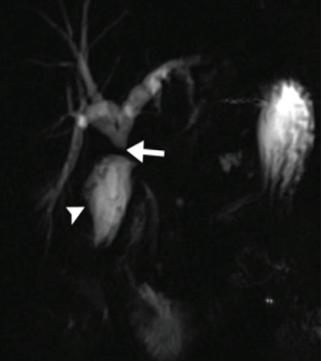

68 НАРАНЯВАНИЯ НА ЖЛЪЧНИТЕ ПЪТИЩА В ХОДА НА ХОЛЕЦИСТЕКТОМИЯ Г. Костов